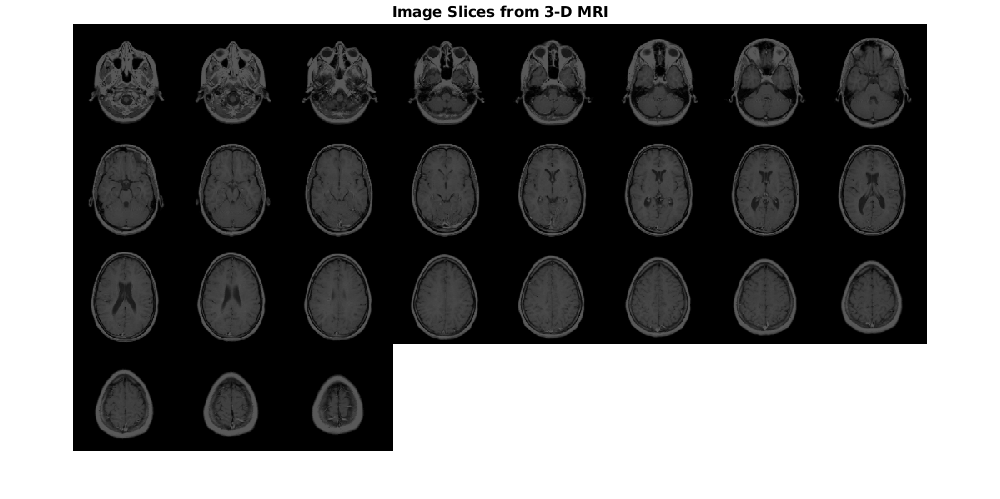

Загрузите и отобразите объем MRI, который будет преобразован.

s = load('mri');

mriVolume = squeeze(s.D);

Отобразите фрагменты изображения от объема входа MRI как монтаж.

montage(mriVolume,'Size',[4 8],'BackgroundColor','w')

title('Image Slices from 3-D MRI','FontSize',14)